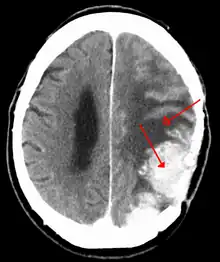

| A contrast-enhanced CT scan of the brain, demonstrating the appearance of a meningioma | |

Meningiomas are visualized readily with contrast CT, MRI with gadolinium,[17] and arteriography, all attributed to the fact that meningiomas are extra-axial and vascularized. CSF protein levels are usually found to be elevated when lumbar puncture is used to obtain spinal fluid.